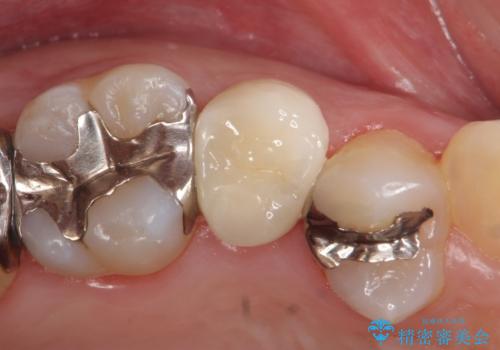

- 頬側から見たとき右上5番目の銀歯が気になるので、オールセラミッククラウンによる補綴を行った症例です。

今回用いたオールセラミッククラウンはジルコニアフレームという白い素材の上にセラミックを盛っているため、審美性が非常に高いのが特徴です。

また、ジルコニアは人工ダイヤモンドの材料にも使われているほど高い強度を持っており、そのためオールセラミッククラウンは審美性だけでなく、奥歯やブリッジの補綴も可能とするクラウンです。